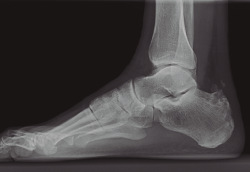

Solo 2 pacientes (13%) requirieron una segunda intervención dada la persistencia de los síntomas al año de la cirugía de GPR. Estos 2 pacientes presentaban casos de Haglund con calcificación extensa en el área insercional (Figura 3) que fueron tratados mediante calcaneoplastia: en un caso abierta y en otro caso artroscópica, obteniendo mejoría clínica significativa únicamente en el segundo caso.

Figura 3. Caso con deformidad de Haglund avanzada y calcificaciones en la zona insercional.